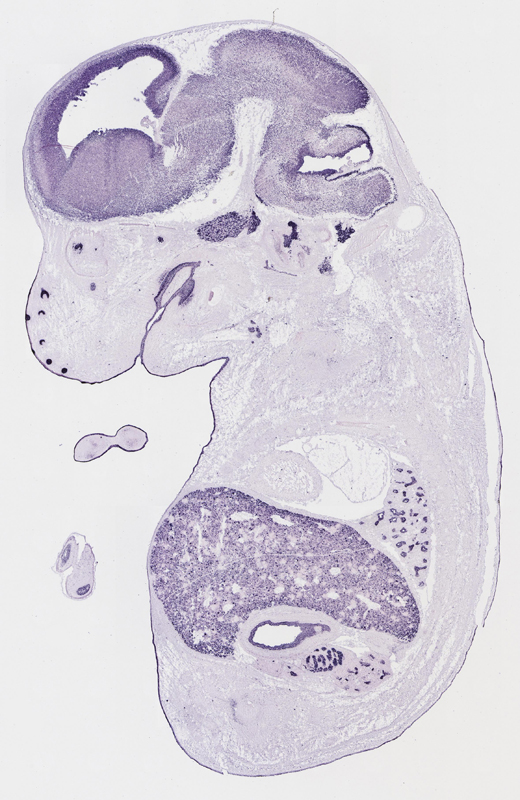

Specimen

euxassay_003287_01:

embryonic day 14.5